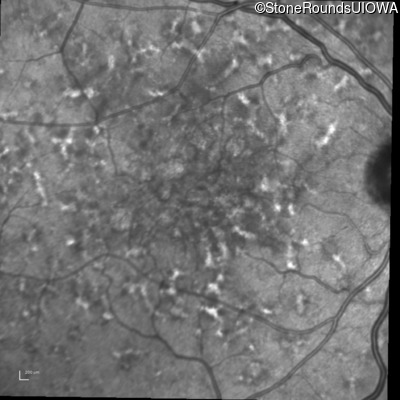

Blue Autofluorescence - Right - 20/20 -1 sc

Exemplar

Blue Autofluorescence - Left - 20/32 sc